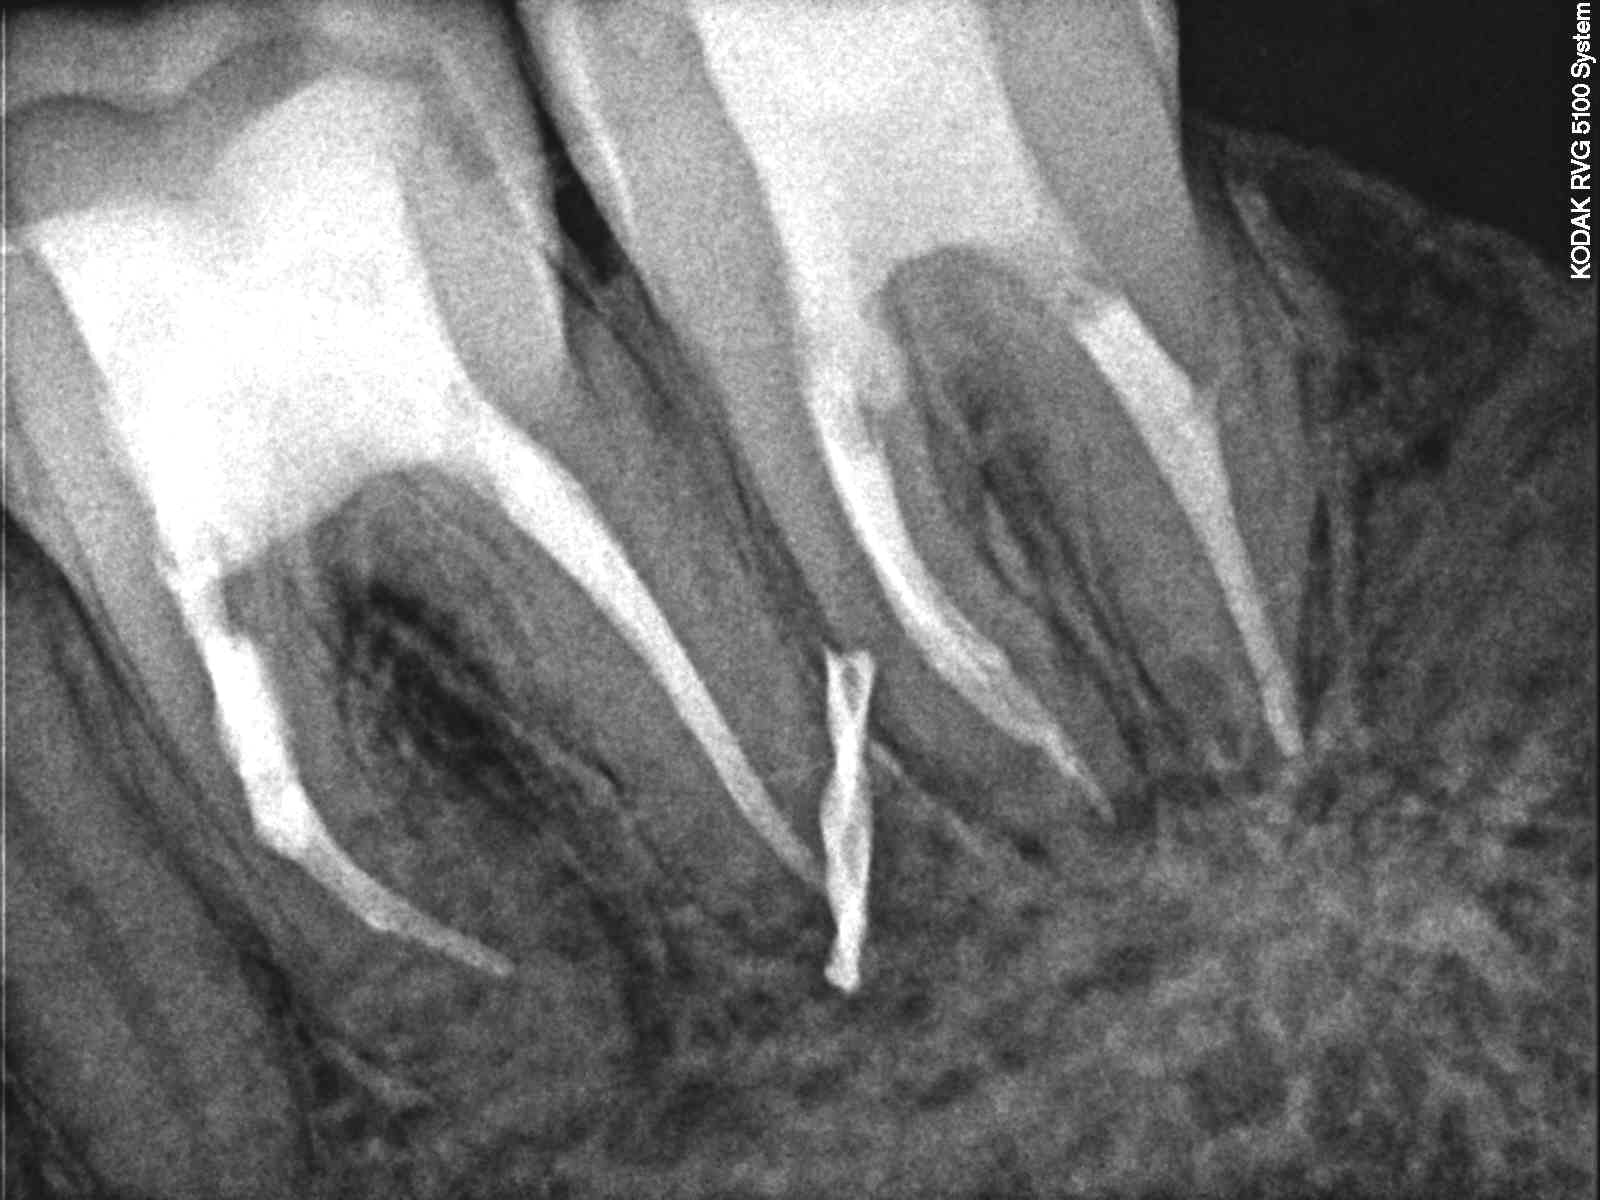

Ryc. 3. Zdjęcie rentgenowskie wykonane po całkowitym usunięciu materiału z systemu kanałowego zęba 36. Na obraz kanałów bliższych nakłada się dobrze kontrastujący materiał. W korzeniu bliższym zęba 37 natomiast widoczny ubytek tkanek nieco poniżej szyjki zęba. Zdjęcie rentgenowskie wykonane z ćwiekiem gutaperkowym wsuniętym do przetoki ropnej, prowadzącym do miejsca przyczynowego.

2. Ząb 37 z martwą miazgą i przetoką na granicy części koronowej i środkowej korzenia bliższego. Zdjęcia rentgenowskie wykonane w gabinecie wykazały perforację korzenia bliższego zlokalizowaną około 3 mm poniżej szyjki zęba, powstałą w wyniki nawiercania kości w celu osadzenia mikroimplantu (druga próba nawiercania) oraz fragment wiertła tkwiący pomiędzy wierzchołkami korzenia dalszego zęba 36 oraz korzenia bliższego zęba 37 (trzecia próba nawiercania) (ryc. 1‑3) (film 1 i2).